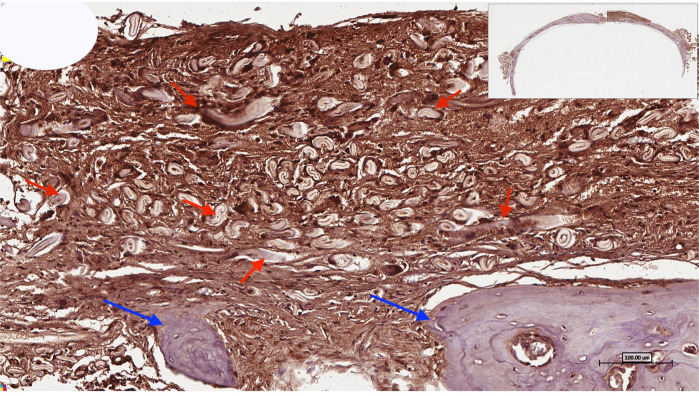

Further clinical experimentations suggest the use of In vivo osteogenic properties for the grafting of skeletal muscles. Such experimentation shows that novel strategies can be implemented to facilitate effective bone regeneration [19, 20, 23]. For example, more recently, it has been established that decellularized skeletal muscles (Fig. 2) can be utilized for bone augmentation to facilitate regeneration and to restore the contour and volume of the lost bone. The experiment also included histological assessment that showed the formation of neovascularization which showed a potential graft strategy for patient presented with massive bone resorption or critical-sized defects [24, 25].

Fig. 2.

Higher-magnification image of the center of the bony defect showing the use of treated, decellularized muscle for the reconstruction of numerous bone spicules (blue arrows) surrounded by connective tissue that shows the positive intake of osteopontin (OPN) immunostaining